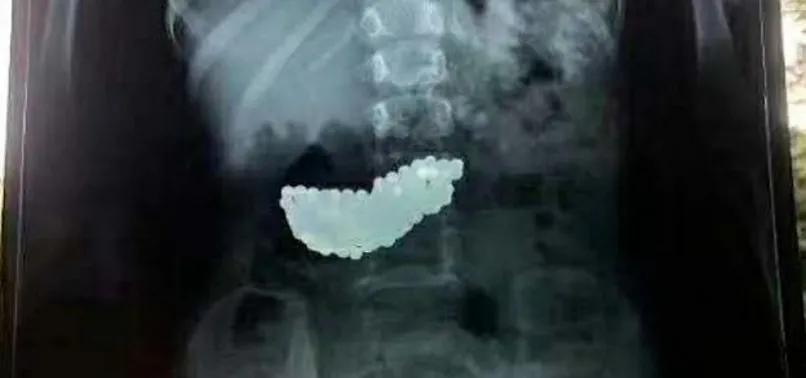

Çinli bir çocuğun midesinden, 190 adet mıknatıslı bilye çıkartıldı. 5 yaşındaki çocuğun, oyun oynarken bilyeleri yuttuğu ve 2 ay boyunca midesinde bu bilyelerle yaşadığı ortaya çıktı.

Mıknatıslı olan bilyeler çocuğun midesinde biraraya gelerek büyük bir kitle haline geldi.

Bilyeler doğal yollardan çıkmayınca küçük kız 2 ay bu kitleyle yaşadı. Doktorlar rontgenle tespit ettikleri kitleyi ameliyatla çıkardı.